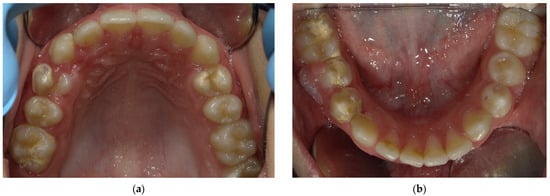

2.2. Clinical Findings

2.5. Follow-Up and Outcomes

3. Results